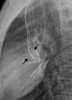

Transposition of great vessels with interatrial communication

Transposition of great vessels